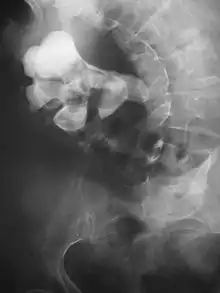

Calcium-containing stones are relatively radiodense, and they can often be detected by a traditional radiograph of the abdomen that includes the kidneys, ureters, and bladder (KUB film).[58] KUB radiograph, although useful in monitoring size of stone or passage of stone in stone formers, might not be useful in the acute setting due to low sensitivity.[59] Some 60% of all renal stones are radiopaque.[60][61] In general, calcium phosphate stones have the greatest density, followed by calcium oxalate and magnesium ammonium phosphate stones. Cystine calculi are only faintly radiodense, while uric acid stones are usually entirely radiolucent.[62]

Bilateral kidney stones can be seen on this KUB radiograph. There are phleboliths in the pelvis, which can be misinterpreted as bladder stones.